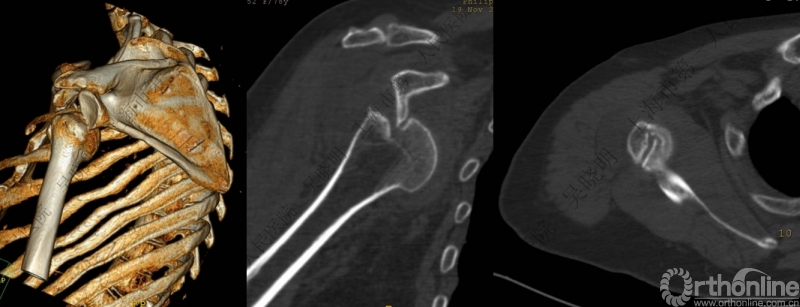

特别警惕伴肱骨头外翻合并大结节骨折的肩关节脱位

警惕:有无肱骨头外翻

伴大结节骨折的老年性肩关节前脱位伴肱骨头外翻

肩关节前脱位合并大结节骨折&肱骨头外翻:外翻压缩型(Neer 分型)

对这型骨折进行手法复位会导致肱骨头和肱骨干之间的连续性消失。肱骨头和肱骨干之间连续性尚存,肱骨头前脱位(Robsion 3b)

必需时进一步急诊CT检查